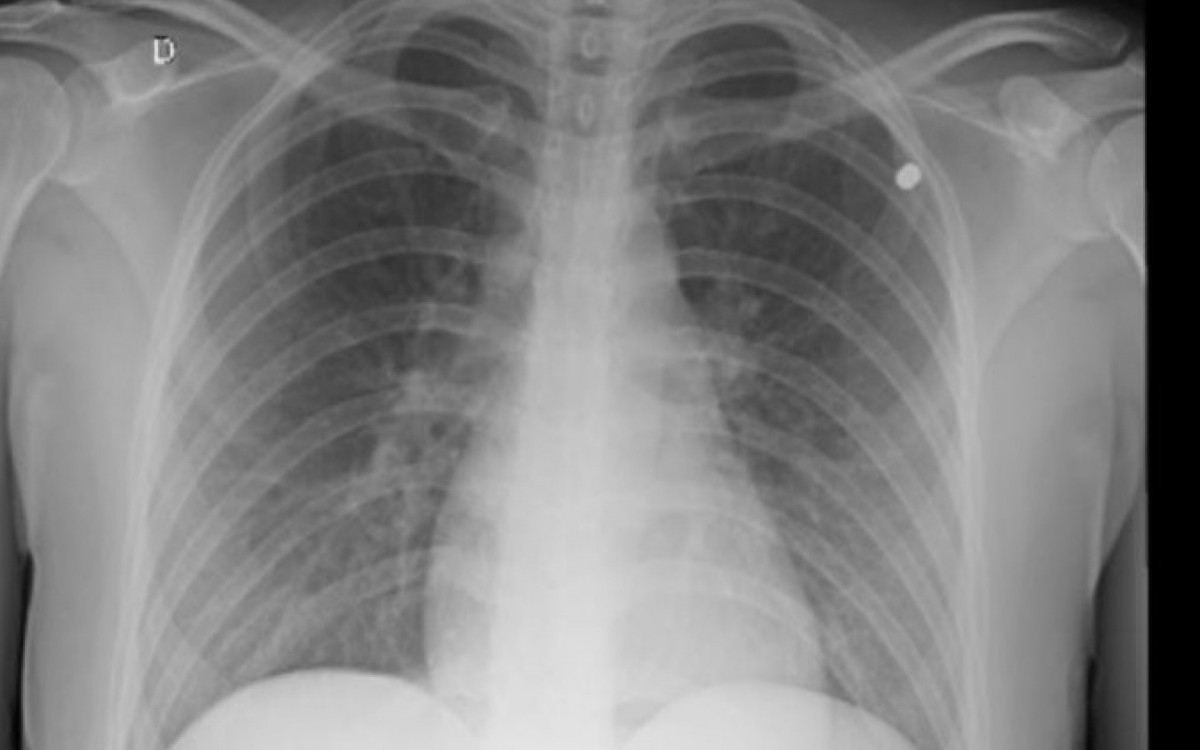

No Hospital Glória D'Or, os atendentes informaram que era possível sentir, ao toque, que havia um objeto dentro do corpo dela. Com uma radiografia, os médicos conseguiram enxergar o pequeno projétil localizado no tórax. "Na delegacia, fui encaminhada para o Instituto Médico Legal (IML), onde um perito pediu para que eu retornasse depois que conseguisse retirar o objeto. Amanhã [terça-feira], tenho uma consulta para agendar a retirada e ver se realmente foi uma arma de chumbinho. A gente desconfia que tenha sido porque já aconteceu uma situação parecida na Praça Paris", contou a profissional de RH, que completou: